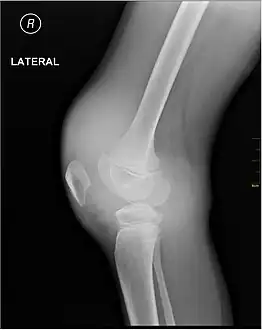

X-ray of Hemarthrosis

Synovial Fluid analysis is another method to diagnose Hemarthrosis. It involves a small needle being inserted into the joint to draw the fluid.[8] Reddish-colored hue of the sample is an indication of the blood being present. Imaging tests are normally done. The tests also include MRI, Ultrasound and X-ray test, which give better information about the joint inflammation.[9]